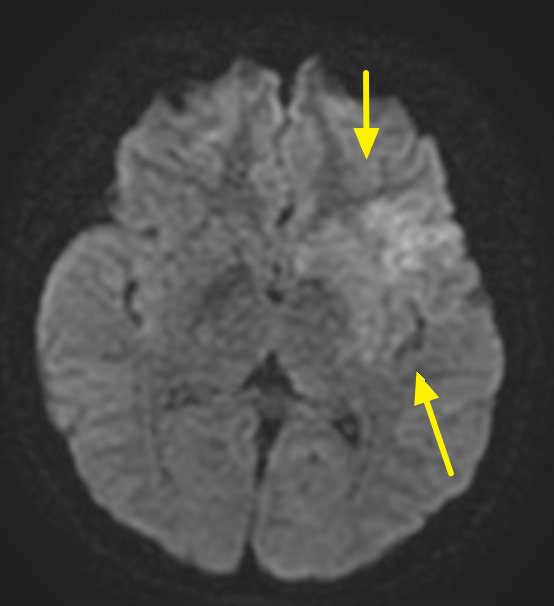

郭葉璘說明,左側大腦掌管語言中樞、身體右側活動能力及視覺與空間感知區域,中大腦動脈是負責供應大腦三分之二的重要血流。磁振造影中的擴散權重影像序列(DWI),能在中風發生後30分鐘內偵測腦部受損區域。檢查顯示該學生的左側中大腦動脈完全阻塞,磁振中的擴散權重影像序列也出現一塊淡淡的受損區域,這表示阻塞的危險性正快速提高中。若不即時處理,這片受損區域會持續擴大,腦部將因血栓壓迫而腫脹,同時往下壓迫腦幹,危及呼吸與心跳中樞,甚至造成生命危險。